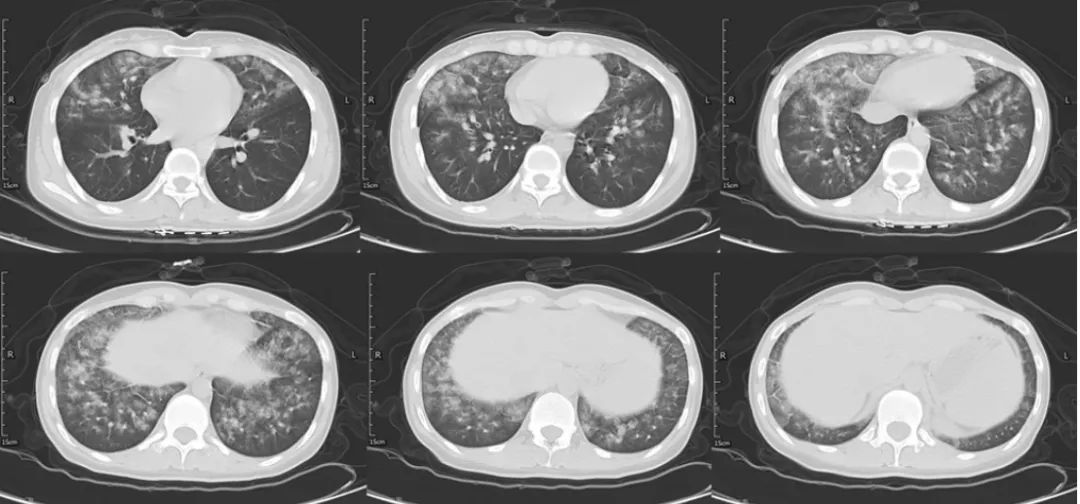

患者胸部CT示双肺上叶及中下叶均有磨玻璃影,部分呈腺泡结节,融合成片。

29岁女性,2021年2月入院。间断发热3个月,进行性呼吸困难23天。患者3个月前(2020年12月)出现间断发热,傍晚发热为主,Tmax 38.5℃,伴轻微咳嗽,查胸部CT未见明显异常,口服中成药治疗,仍有间断发热。1月余前再次因发热就诊于当地医院,复查CT示“双肺多发小结节,考虑纤维灶可能”,查血WBC、N%、CRP、ESR升高,予以咳嗽糖浆治疗,仍发热。

3周前患者再次发热,伴剧烈咳嗽、咯血痰,量不多,伴明显呼吸困难,再次就诊于当地医院急诊,查CT提示“双肺炎性病变,右侧胸腔积液,左侧胸膜渗液,双肺多发小结节”,血常规提示WBC 14.04×109/L,NEUT 12.4×109/L,CRP 21.58 mg/L;鼻导管吸氧10 L/min时指尖氧饱和度波动于70%左右,诊断“重症肺炎,右侧胸腔积液”收入ICU。

患者呼吸困难持续加重,无创呼吸机耐受差,伴血压下降,考虑“重症肺炎,感染性休克,急性呼吸窘迫综合征ARDS)”,当日行气管插管有创机械通气、去甲肾上腺素升压,插管后经口吸出血性物,更换为美罗培南联合阿奇霉素抗感染,奥司他韦抗病毒等治疗。送检痰NGS:嗜麦芽窄食单胞菌、木糖氧化无色杆菌、霍氏肠杆菌、白念珠菌、人类α疱疹病毒Ⅰ型。血NGS:人类α疱疹病毒Ⅰ型。